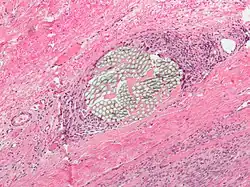

Giant cell arteritis

Giant cell arteritis,[6] also known as temporal arteritis or cranial arteritis, is the most common MGC-linked disease. This type of arteritis causes the arteries in the head, neck, and arm area to swell to abnormal sizes. Although the cause of this disease is not currently known, it appears to be related to polymyalgia rheumatica.[7]

Giant cell arteritis is most prevalent in older individuals, with the rate of disease being seen to increase from age 50. Women are 2–3 times more likely to develop the disease than men.

Northern Europeans have been observed to have a higher incidence of giant cell arteritis compared to southern European, Hispanic, and Asian populations. It has been suggested that this difference may lie in the criteria used to diagnose giant cell arteritis rather than actual disease incidence, in addition to genetic and geographic factors.[8]

The current highest standard for diagnosis is a temporal artery biopsy.[12] The skin on the patient's face is anesthetized, and an incision is made in the face around the area of the temples to obtain a sample of the temporal artery. The incision is then sutured. A histopathologist examines the sample under a microscope and issues a pathology report (pending extra tests that may be requested by the pathologist).